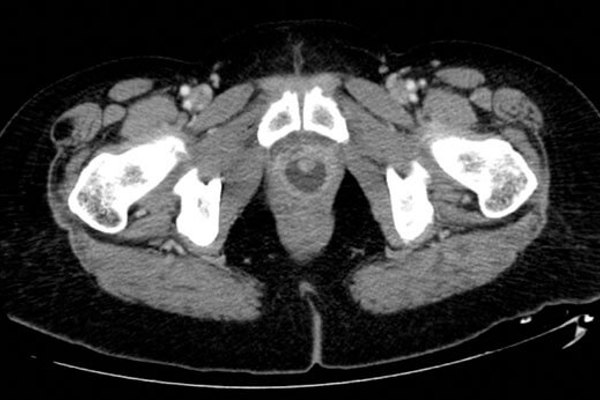

Infection

Infections and inflammation: Part 3